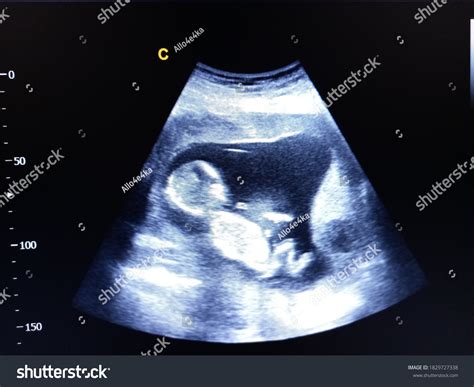

A 14 week ultrasound is typically performed between 13 weeks and 14 weeks of pregnancy. It is often referred to as the “nuchal translucency” scan because it measures the thickness of fluid behind the baby’s neck. This measurement, along with other factors, can help assess the risk of certain chromosomal abnormalities, such as Down syndrome.

During the 14 week ultrasound, you will lie on an examination table with your abdomen exposed. The technician will apply a gel to your belly and use a transducer to capture images of your baby. The procedure is painless and usually takes about 20-30 minutes.

Heartbeat The baby’s heartbeat should be strong and regular, usually between 120 and 160 beats per minute.

Nuchal Translucency This measurement helps assess the risk of chromosomal abnormalities. A thicker measurement may indicate a higher risk.

Anatomy The technician will check for the presence of all major organs, including the brain, heart, stomach, and kidneys.

Placenta The position of the placenta will be noted to ensure it is not covering the cervix, which could lead to complications later in pregnancy.

Amniotic Fluid The amount of amniotic fluid will be assessed to ensure it is within normal ranges.